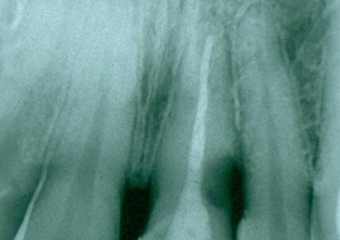

Rx Periapical Inicial 15-06-15